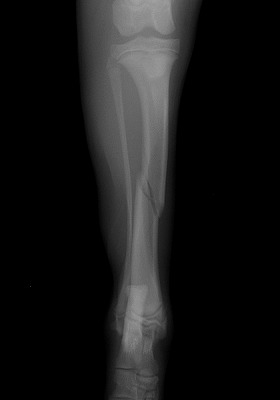

家の中で遊んでいると「キャイーン」という悲鳴と共に片方の足を地面に付く事が出来なくなり来院されました。レントゲンを撮り調べてみると骨折していることが判明。

手術をして元の状態に骨を整復しました。